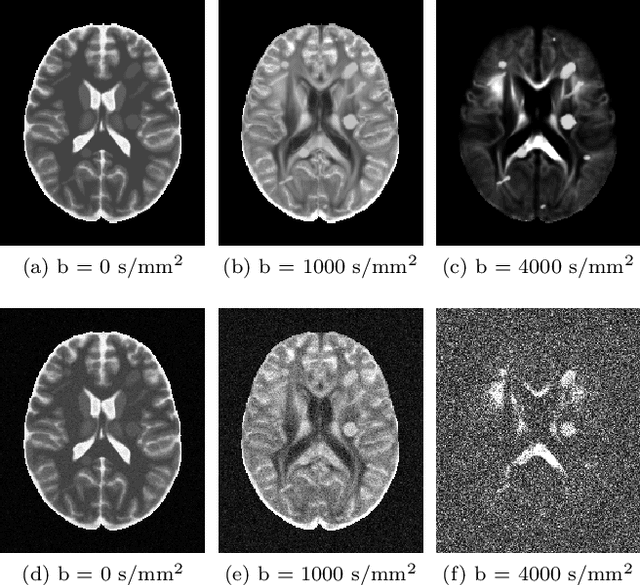

Abstract:Water diffusion gives rise to micrometer-scale sensitivity of diffusion MRI (dMRI) to cellular-level tissue structure. The advent of precision medicine and quantitative imaging hinges on revealing the information content of dMRI, and providing its parsimonious basis- and hardware-independent "fingerprint". Here we reveal the geometry of a multi-dimensional dMRI signal, classify all 21 invariants of diffusion and covariance tensors in terms of irreducible representations of the group of rotations, and relate them to tissue properties. Previously studied dMRI contrasts are expressed via 7 invariants, while the remaining 14 provide novel complementary information. We design acquisitions based on icosahedral vertices guaranteeing minimal number of measurements to determine 3-4 most used invariants in only 1-2 minutes for the whole brain. Representing dMRI signals via scalar invariant maps with definite symmetries will underpin machine learning classifiers of brain pathology, development, and aging, while fast protocols will enable translation of advanced dMRI into clinical practice.